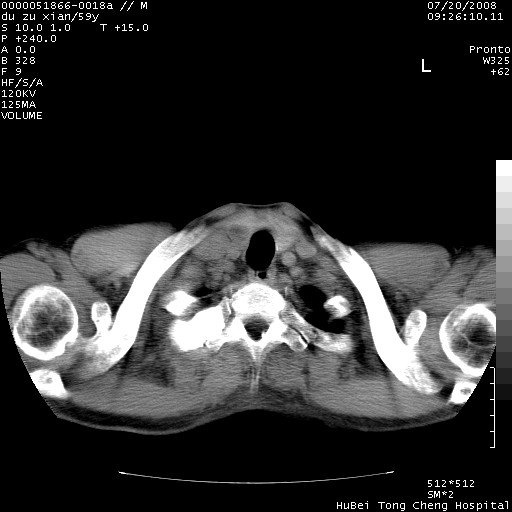

以下是引用宇宙ct在2008-8-25 23:21:00的发言:[br]右肺周围性肺癌并肋骨转移,纵隔淋巴结转移。

以下是引用zsl6918在2008-8-25 22:40:00的发言:[br]右肺周围性肺癌并肋骨转移,纵隔淋巴结转移。

以下是引用zy_zj在2008-8-26 15:24:00的发言:[br]单从病变本身,我倾向良性炎性病变,但肋骨转移了,所以说是考虑右肺周围性肺癌并肋骨、纵隔淋巴结转移可能性大。